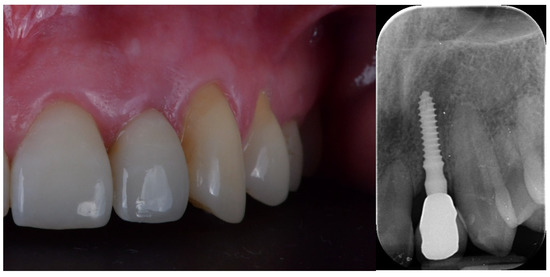

- Any biological complications (e.g., pain, swelling, mobility, suppuration) and/or technical issues (e.g., material fractures, screw loosening) were reported during follow-up;

- Esthetic evaluation of clinical pictures, including at least two adjacent teeth, taken at two years after loading was done following the pink esthetic score (PES) proposed by Fürhauser et al., in 2005 [31]. In brief, the PES score evaluates seven variables: mesial papilla, distal papilla, soft tissue level, soft tissue contour, alveolar process deficiencies, soft tissue color and texture. A 0-1-2 scoring system was used, with a maximum achievable score of 14 per site.

| PES 3 at the 2-year follow-up | 12.6 ± 0.97 | 12.2 ± 0.92 | 0.3554 |

| MBL4 at the 2-year follow-up | 0.23 ± 0.11 | 0.18 ± 0.12 | 0.3339 |